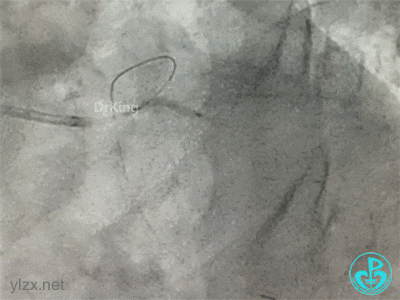

冠脉造影

右冠脉近中段不规则狭窄。短左主干中度狭窄,前降支开口严重狭窄,多功能造影导管推注造影剂时无反流,导管退出左主干开口造影发现左主干狭窄严重。

更换指引导管,导丝分别进入前降支和回旋支,球囊分别扩张前降支开口和回旋支开口,IVUS确认左主干及分支开口病变,前降支中段植入支架,对角支开口球囊扩张。